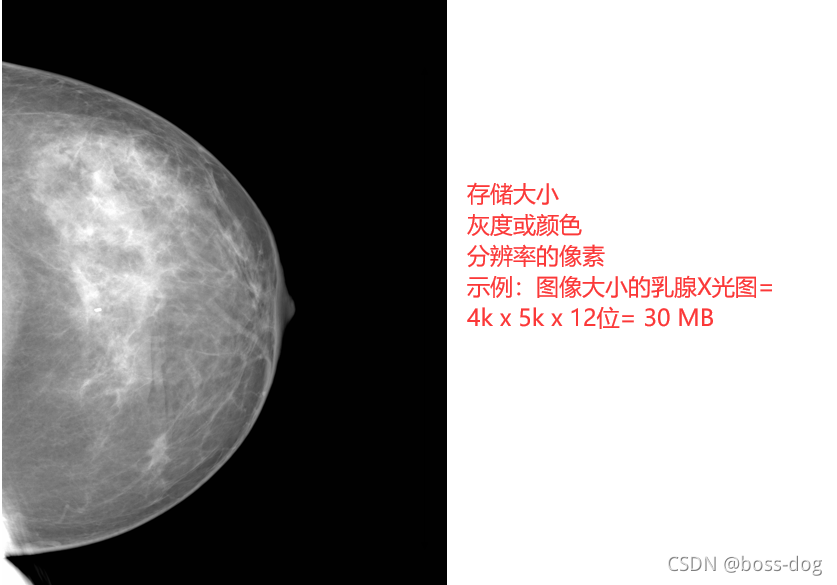

图像质量:分辨率和存储大小

彩色的/单色的

-

图像尺寸x号的图片